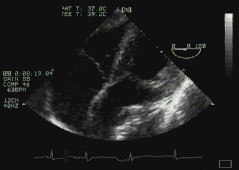

5. ME Long axis - 'ME LAX'

6. The following view is sub-optimal, as the view of the ventricle is somewhat oblique, and the aortic valve isn't well seen.